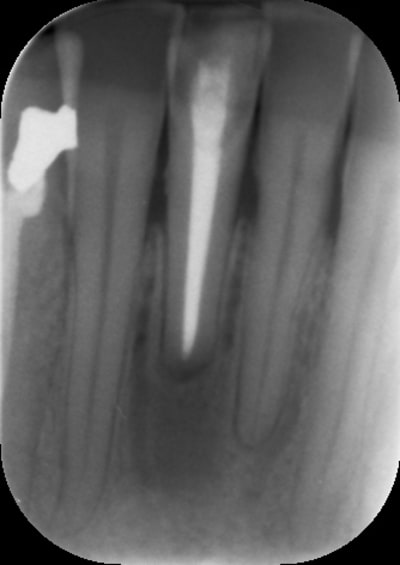

un ami à moi me consulte pour sa 41 qu'il trouve trop lingualée et dyschromiée. Je lui propose à priori de lui réaliser une couronne céramo-céramique, mais aux examens clinique et radiographique, je lui dit que finalement "il faut que je réfléchisse....". D'où mon intervention dans Eugenol. Peut-être pouvez-vous m'aider à trouver LA bonne solution.

L'apex de cette dent est dans le vide...

1 : c est l impact de l apex qu on voit en vestibulaire? RTE utile? (la bio a l air bonne, et la radioclarté ne serait elle pas due a un passage extra osseux?)

la difference de densité osseuse autour de l apex pourrait elle etre due a la remineralisation d une ancienne lesion?

Pour moi, la différence de minéralisation apicale est due à une absence importante, voir total d'os vestibulaire. Il n'y a pas de lésion, le ligament étant bien individualisé. Il y a très peu de risque que ça pose problème un jour. La seule précaution à prendre est de bien vérifier si le fond de la concavité gingivale est bien fermé. Dans ce cas, un éclaircissement interne devrait plus lui plaire que l'implant.

NB : un cone beam confirmerai que j'ai raison.... ;-)

Plutôt d'accord avec cette analyse, on note cependant une petite lésion et vu le manque d'os en vestibulaire, est-ce que la chir apicale est possible? Pour ce qui savent comment gérer une telle chir?.....Membrane? MTA?

La dent n'est pas mobile, asymptomatique. Je pense que l'image est dûe à une absence pratiquement totale d'os vestibulaire et non à la guérison d'une lésion (je suis le patient depuis des années).